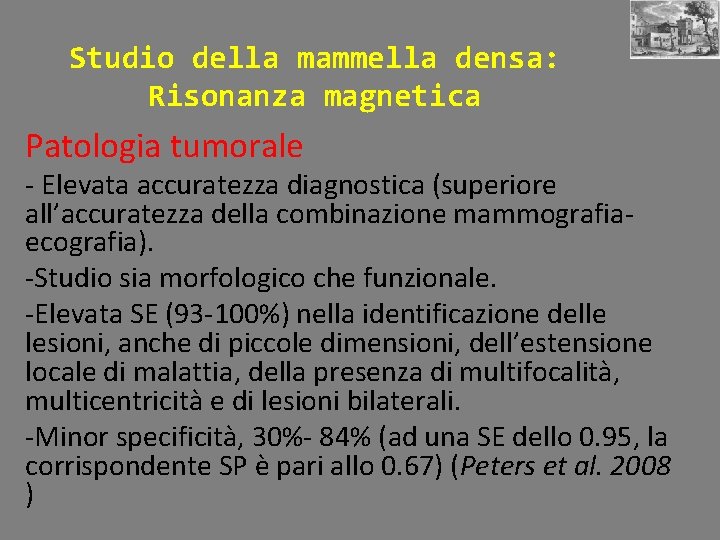

Studio della mammella densa: Risonanza magnetica Patologia tumorale - Elevata accuratezza diagnostica (superiore all’accuratezza della combinazione mammografiaecografia). -Studio sia morfologico che funzionale. -Elevata SE (93 -100%) nella identificazione delle lesioni, anche di piccole dimensioni, dell’estensione locale di malattia, della presenza di multifocalità, multicentricità e di lesioni bilaterali. -Minor specificità, 30%- 84% (ad una SE dello 0. 95, la corrispondente SP è pari allo 0. 67) (Peters et al. 2008 )